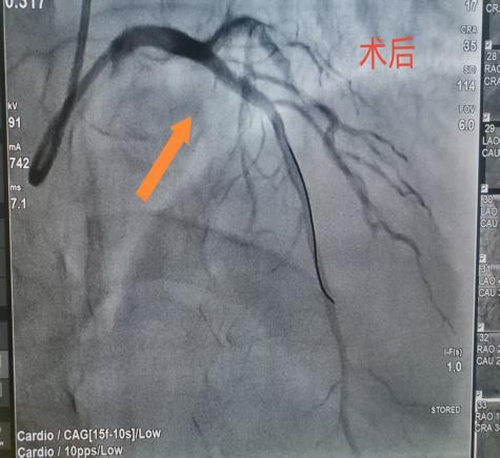

据悉,该患者因粗大前降支近段闭塞,遭受严重胸痛折磨。在接受急诊手术过程中,情况急转直下,患者突然意识丧失,心电监测显示室颤——这是一种极其危险的心律失常,如不及时处理,患者生命将在短时间内消逝。面对这一危急情况,心血管病科团队迅速反应,立即启动电除颤抢救。医护人员争分夺秒,精准操作,与死神展开了一场惊心动魄的较量。紧接着,团队成员凭借丰富的临床经验和高超的介入技术,快速完成导丝通过及支架植入,成功实现血管再通。手术的每一个环节都紧密衔接,每一个操作都精准无误,为患者的生命赢得了宝贵的时间。术后,患者逐渐苏醒,他心有余悸地感慨:“仿佛经历了一次生死轮回。”目前,患者康复状况良好,为表达对心血管病科团队的感激之情,患者特意送来一面锦旗。